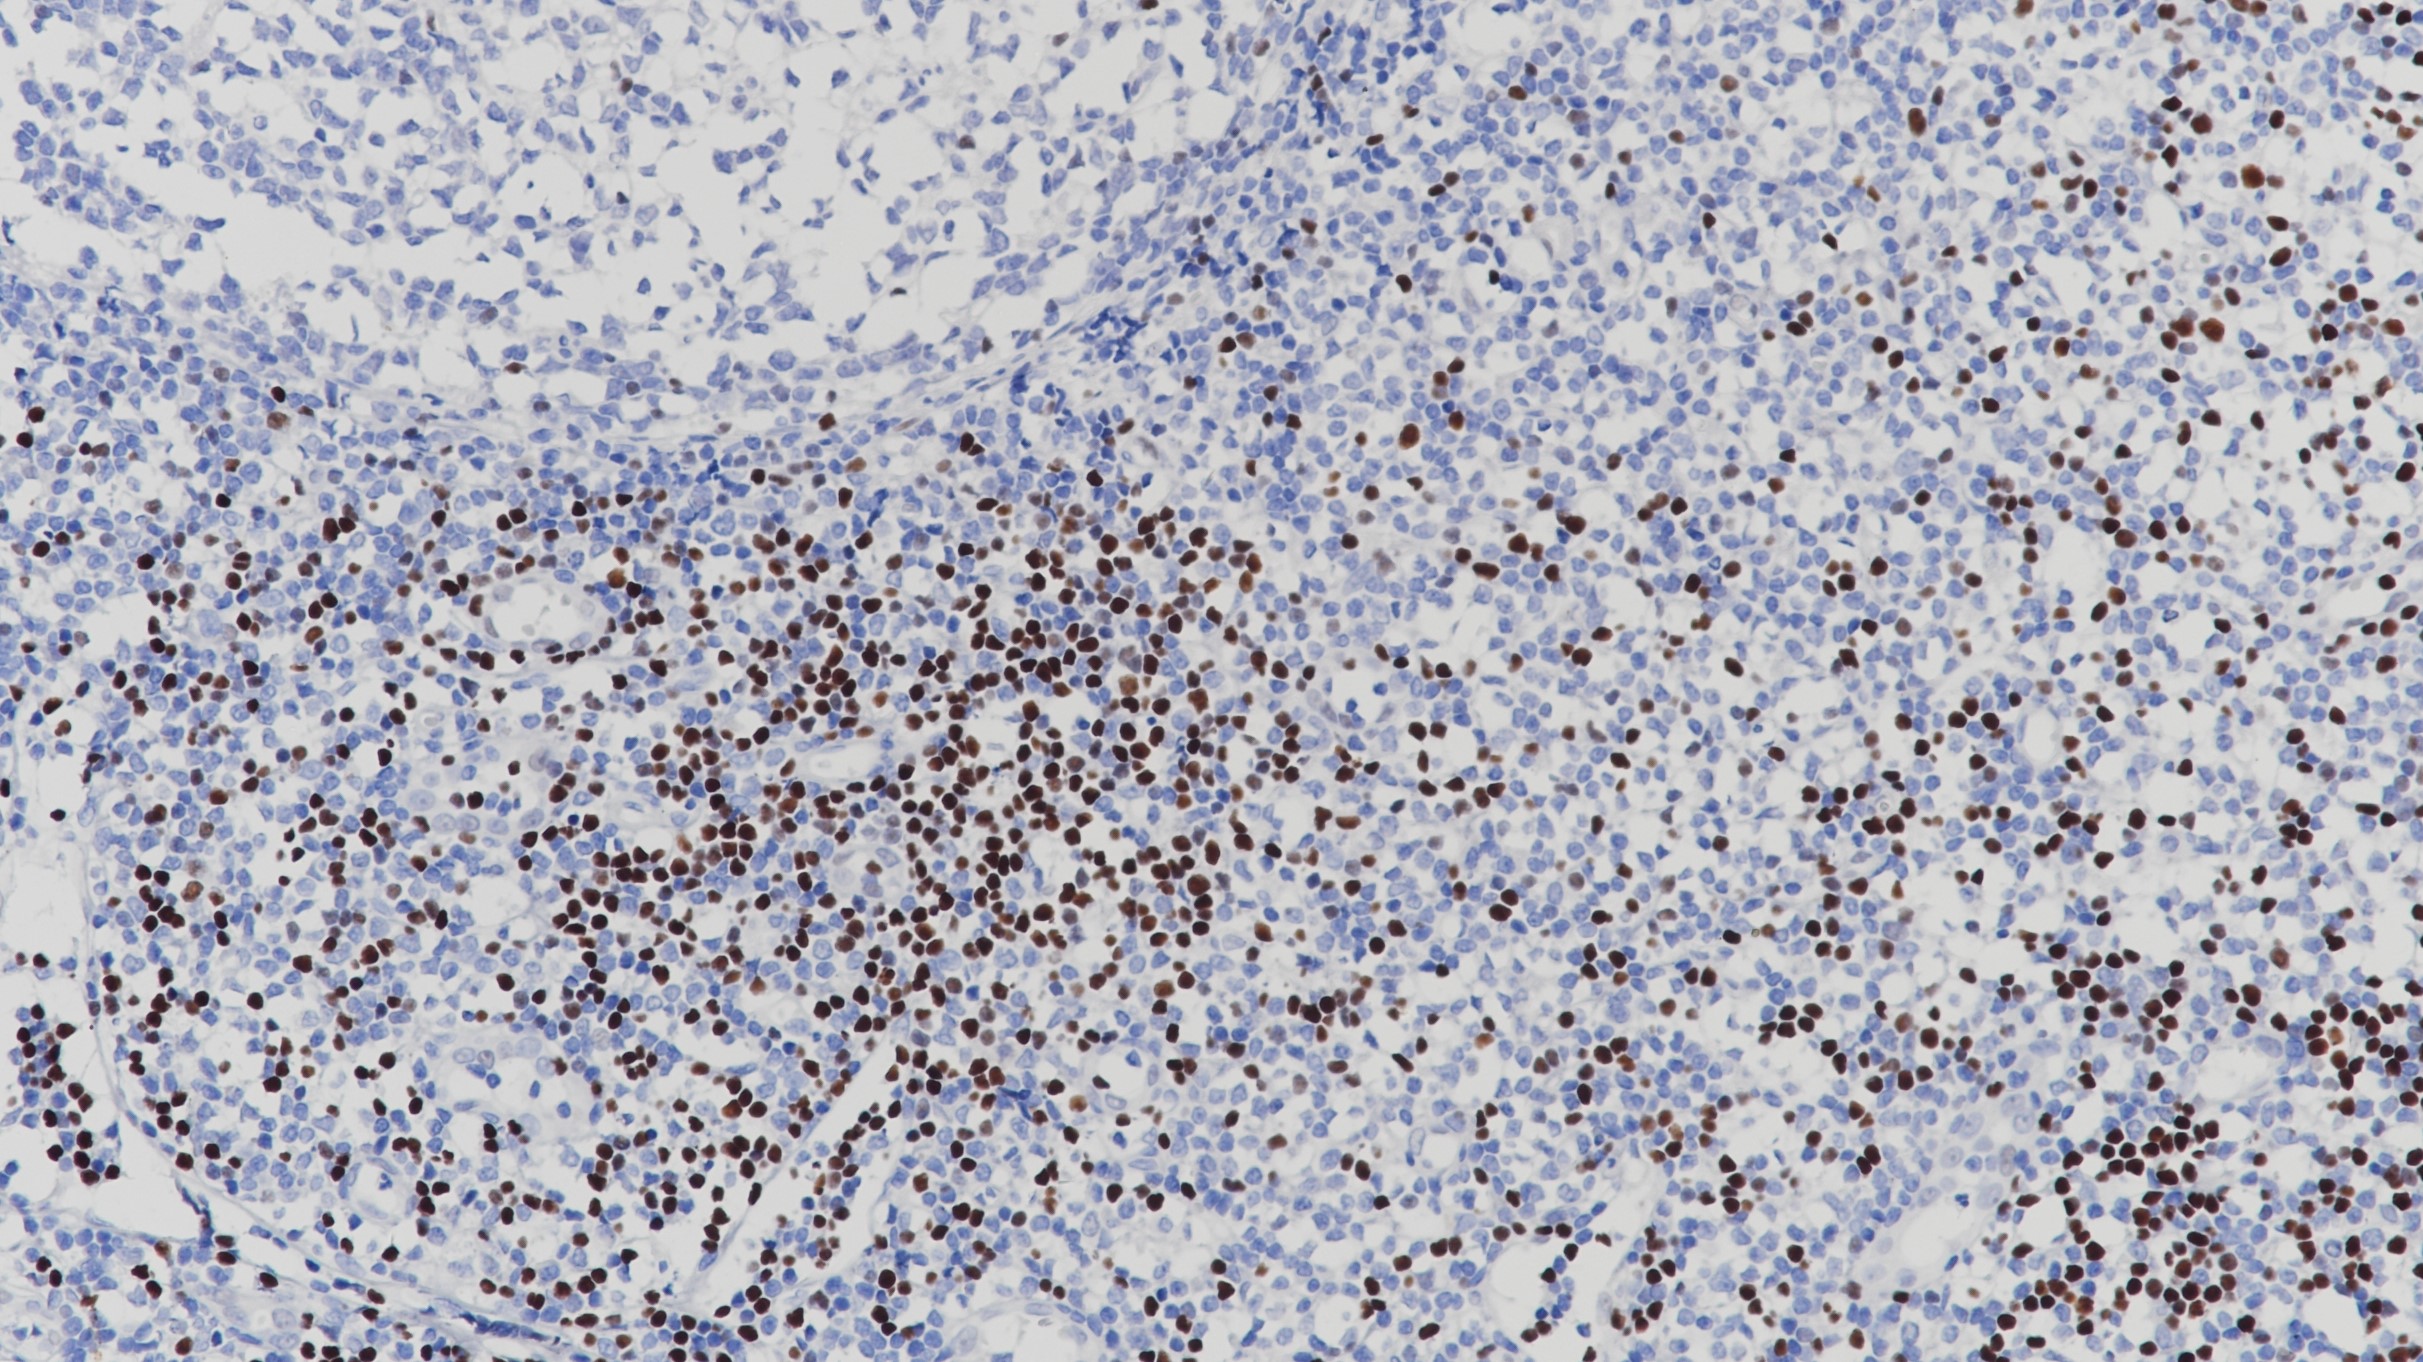

2.Gandhirajan RK, et al. Small Molecule Inhibitors of Wnt/β-Catenin/Lef-1 Signaling Induces Apoptosis in Chronic Lymphocytic Leukemia Cells In Vitro and In Vivo. Neoplasia. 2010; 12:326-35.